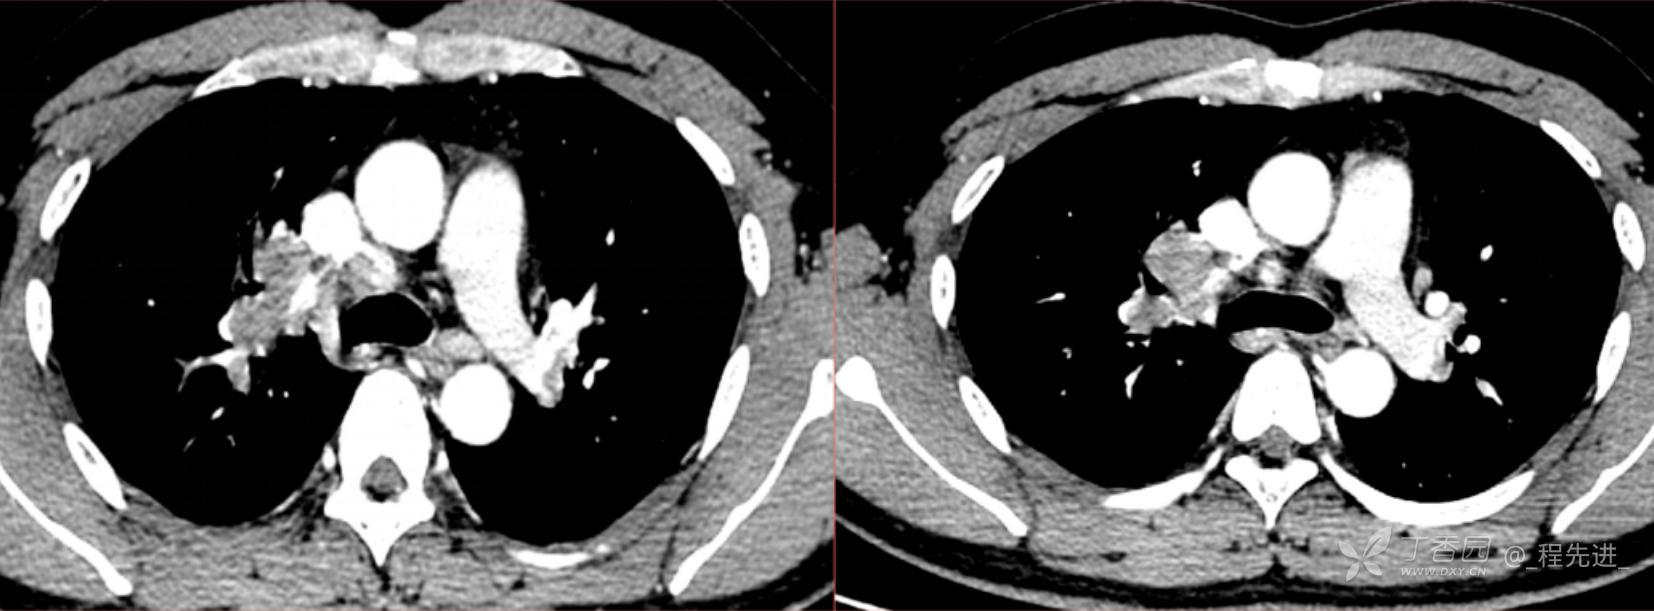

1月特别精彩病例|阵发性刺激性咳嗽,咳少量白色粘液痰1周,期待你的挑战【结果公布】

患者年龄:34岁

简要病史:患者一周前无明显诱因出现阵发性刺激性咳嗽,咳少量白色粘液痰,咳嗽无明显昼夜节律性,无发热、畏冷、寒战,无头痛、胸闷、胸痛,自行服药后 (具体不详) 症状无缓解,3天前当地医院胸片检查示右上病变

辅助检查:肺肿瘤标志物: 神经元特异性烯醇化酶(NSE): 35.72ng/ml(参考值0-16.3);非小细胞肺癌相关抗原211、癌胚抗原、糖类抗原125、铁蛋白、鳞状细胞癌抗原未见异常